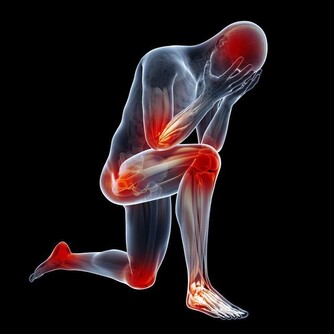

在日常生活中,我們身體免不了會出現一些大大小小的疼痛感,有時候是因為不小心磕傷或者碰撞引起的,有時候什麼毫無感覺身體就出現了一些淤青,這些都有可能是身體的某些疾病引起的,希望大家能重視起來。